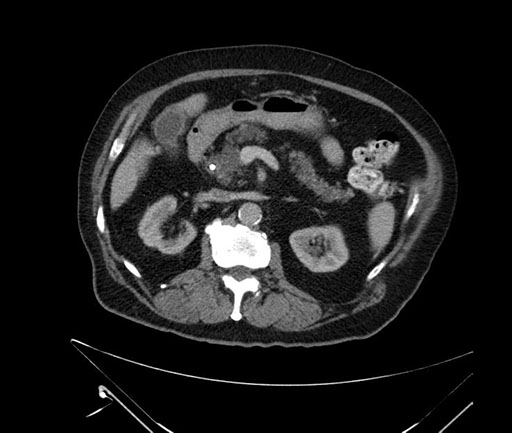

Axial - stented